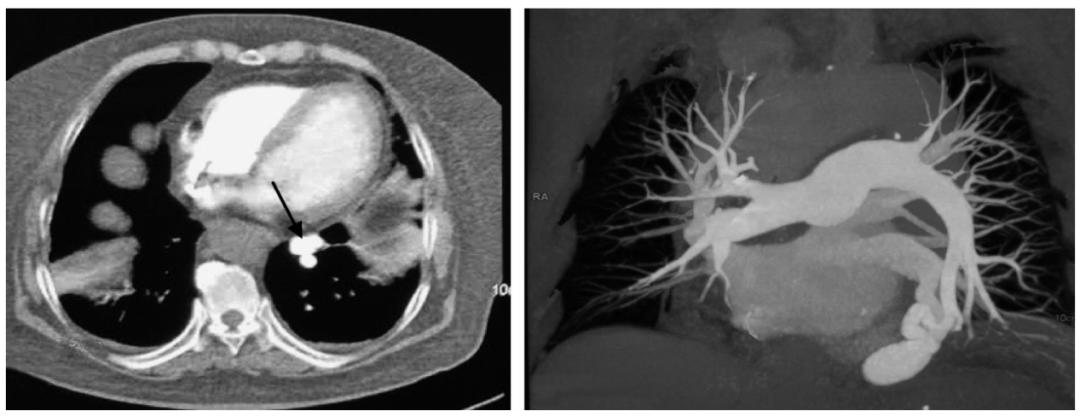

转入我院急诊继续治疗。在就诊过程中再次咯血,达10次以上,量较前增多,约10~ 50ml/次,伴有胸闷、憋气,呼吸困难进行性加重,测BP 119/73mmHg,HR 126次/分,R 49 次/分,SpO283%(未吸氧),遂收入抢救室。入抢救室后予以监护、吸氧、止血、左氧氟沙星抗感染,并立即完善胸主动脉CTA,考虑左下肺存在肺动静脉瘘(图1),胸外科会诊建议介入栓塞治疗,家属拒绝,故暂予内科保守治疗。患者入抢救室后仍有间断咯血,量少,多为痰中带血丝,指氧进行性下降,最低至86%,逐渐升高氧疗条件(由鼻导管升至储氧面罩)方可维持95%以上,再次同家属交代病情及介入治疗的必要性,家属同意介入栓塞治疗,故行胸支气管动脉造影+栓塞术,术中见肺动静脉瘘形成,予以栓塞止血,术后继续给予心电监护及抗感染等治疗。患者未再出现大咯血,监测HGB稳定在120g/L左右,指氧维持在93%~97%(鼻导管吸氧3L/min),病情稳定,遂转入急诊综合病房继续治疗。患者发病以来,饮食、睡眠可,二便正常,体重无明显变化。

图1 患者主动脉CTA结果